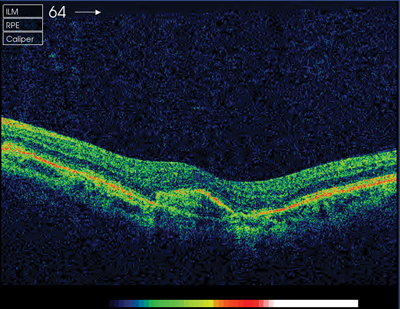

After treatment her vision improved by four lines on logmar, the sub-retinal fluid was resolving bilaterally, and there was evidence of sub-retinal fibrosis in the left eye. Changes in optical coherence tomography (OCT) and FFA are demonstrated in Figures 2-5.

Figure 5: OCT post-injection. © Hanif Patel, Retinal Photographer.